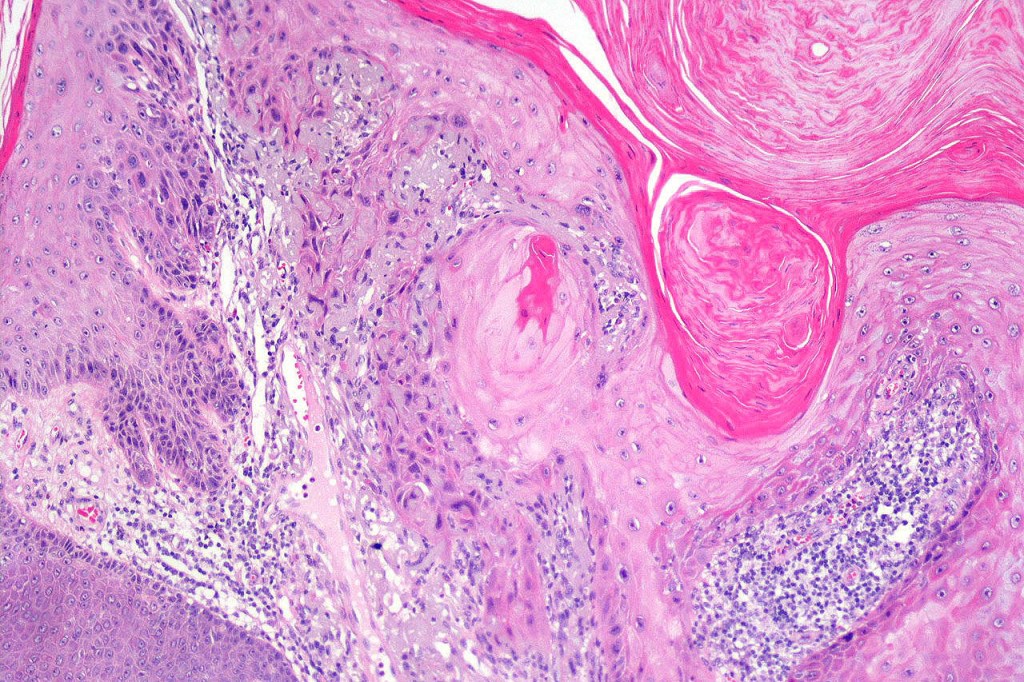

•Keratoacathoma (nowdays regarded as a variant of well differentiated squamous carcinoma) is characterized by a crateriform squamous epithelial lesion (dilated follicular infundibulum) with central keratin plug and adjacent collarette extending to the mid-dermis

•Well differentiated squamous epithelium often with a characteristic ground-glass appearance

•Only mild pleomorphism & basally located mitoses

•Neutrophil-rich microabscesses & necrosis

Below is a fascinating case shared on McKee Derm by Dr. James Simpson. There is an obvious keratoacanthoma but at the edge of the lesion there is marked atypia with nuclear enlargement and pleomorphism. This is also evident in the adjacent epidermis and in the deeper nests.